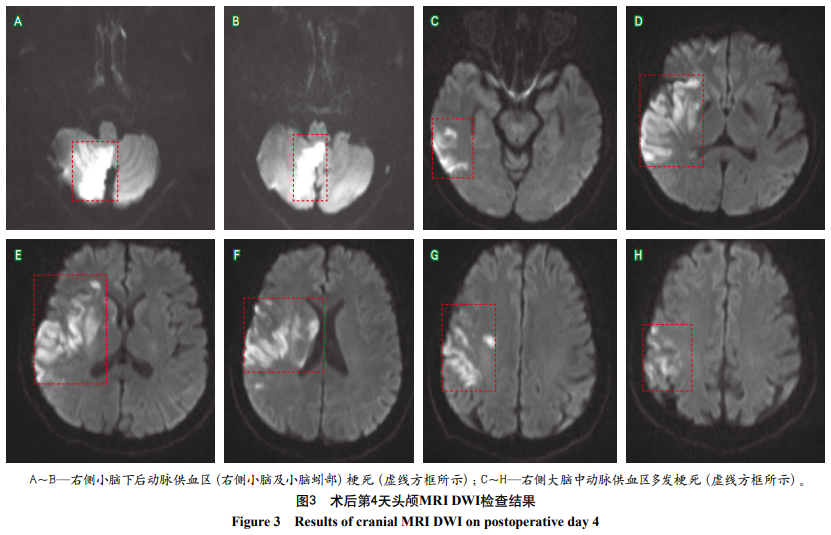

带状疱疹后大血管病变致脑梗死1例

摘要:水痘-带状疱疹病毒(varicella-zoster virus,VZV)再激活与缺血性卒中的发生密切相关,其主要机制包括病毒对脑血管直接侵袭导致的内皮损伤、免疫介导的炎症反应及继发性血栓形成等。本文报道1例52岁女性患者,于右侧颈肩部带状疱疹发病10 d后,相继出现后循环及前循环脑缺血症状。影像学检查显示右侧小脑和大脑半球多发梗死,以及同侧颈内动脉、大脑中动脉闭塞,经机械取栓后患者血管部分